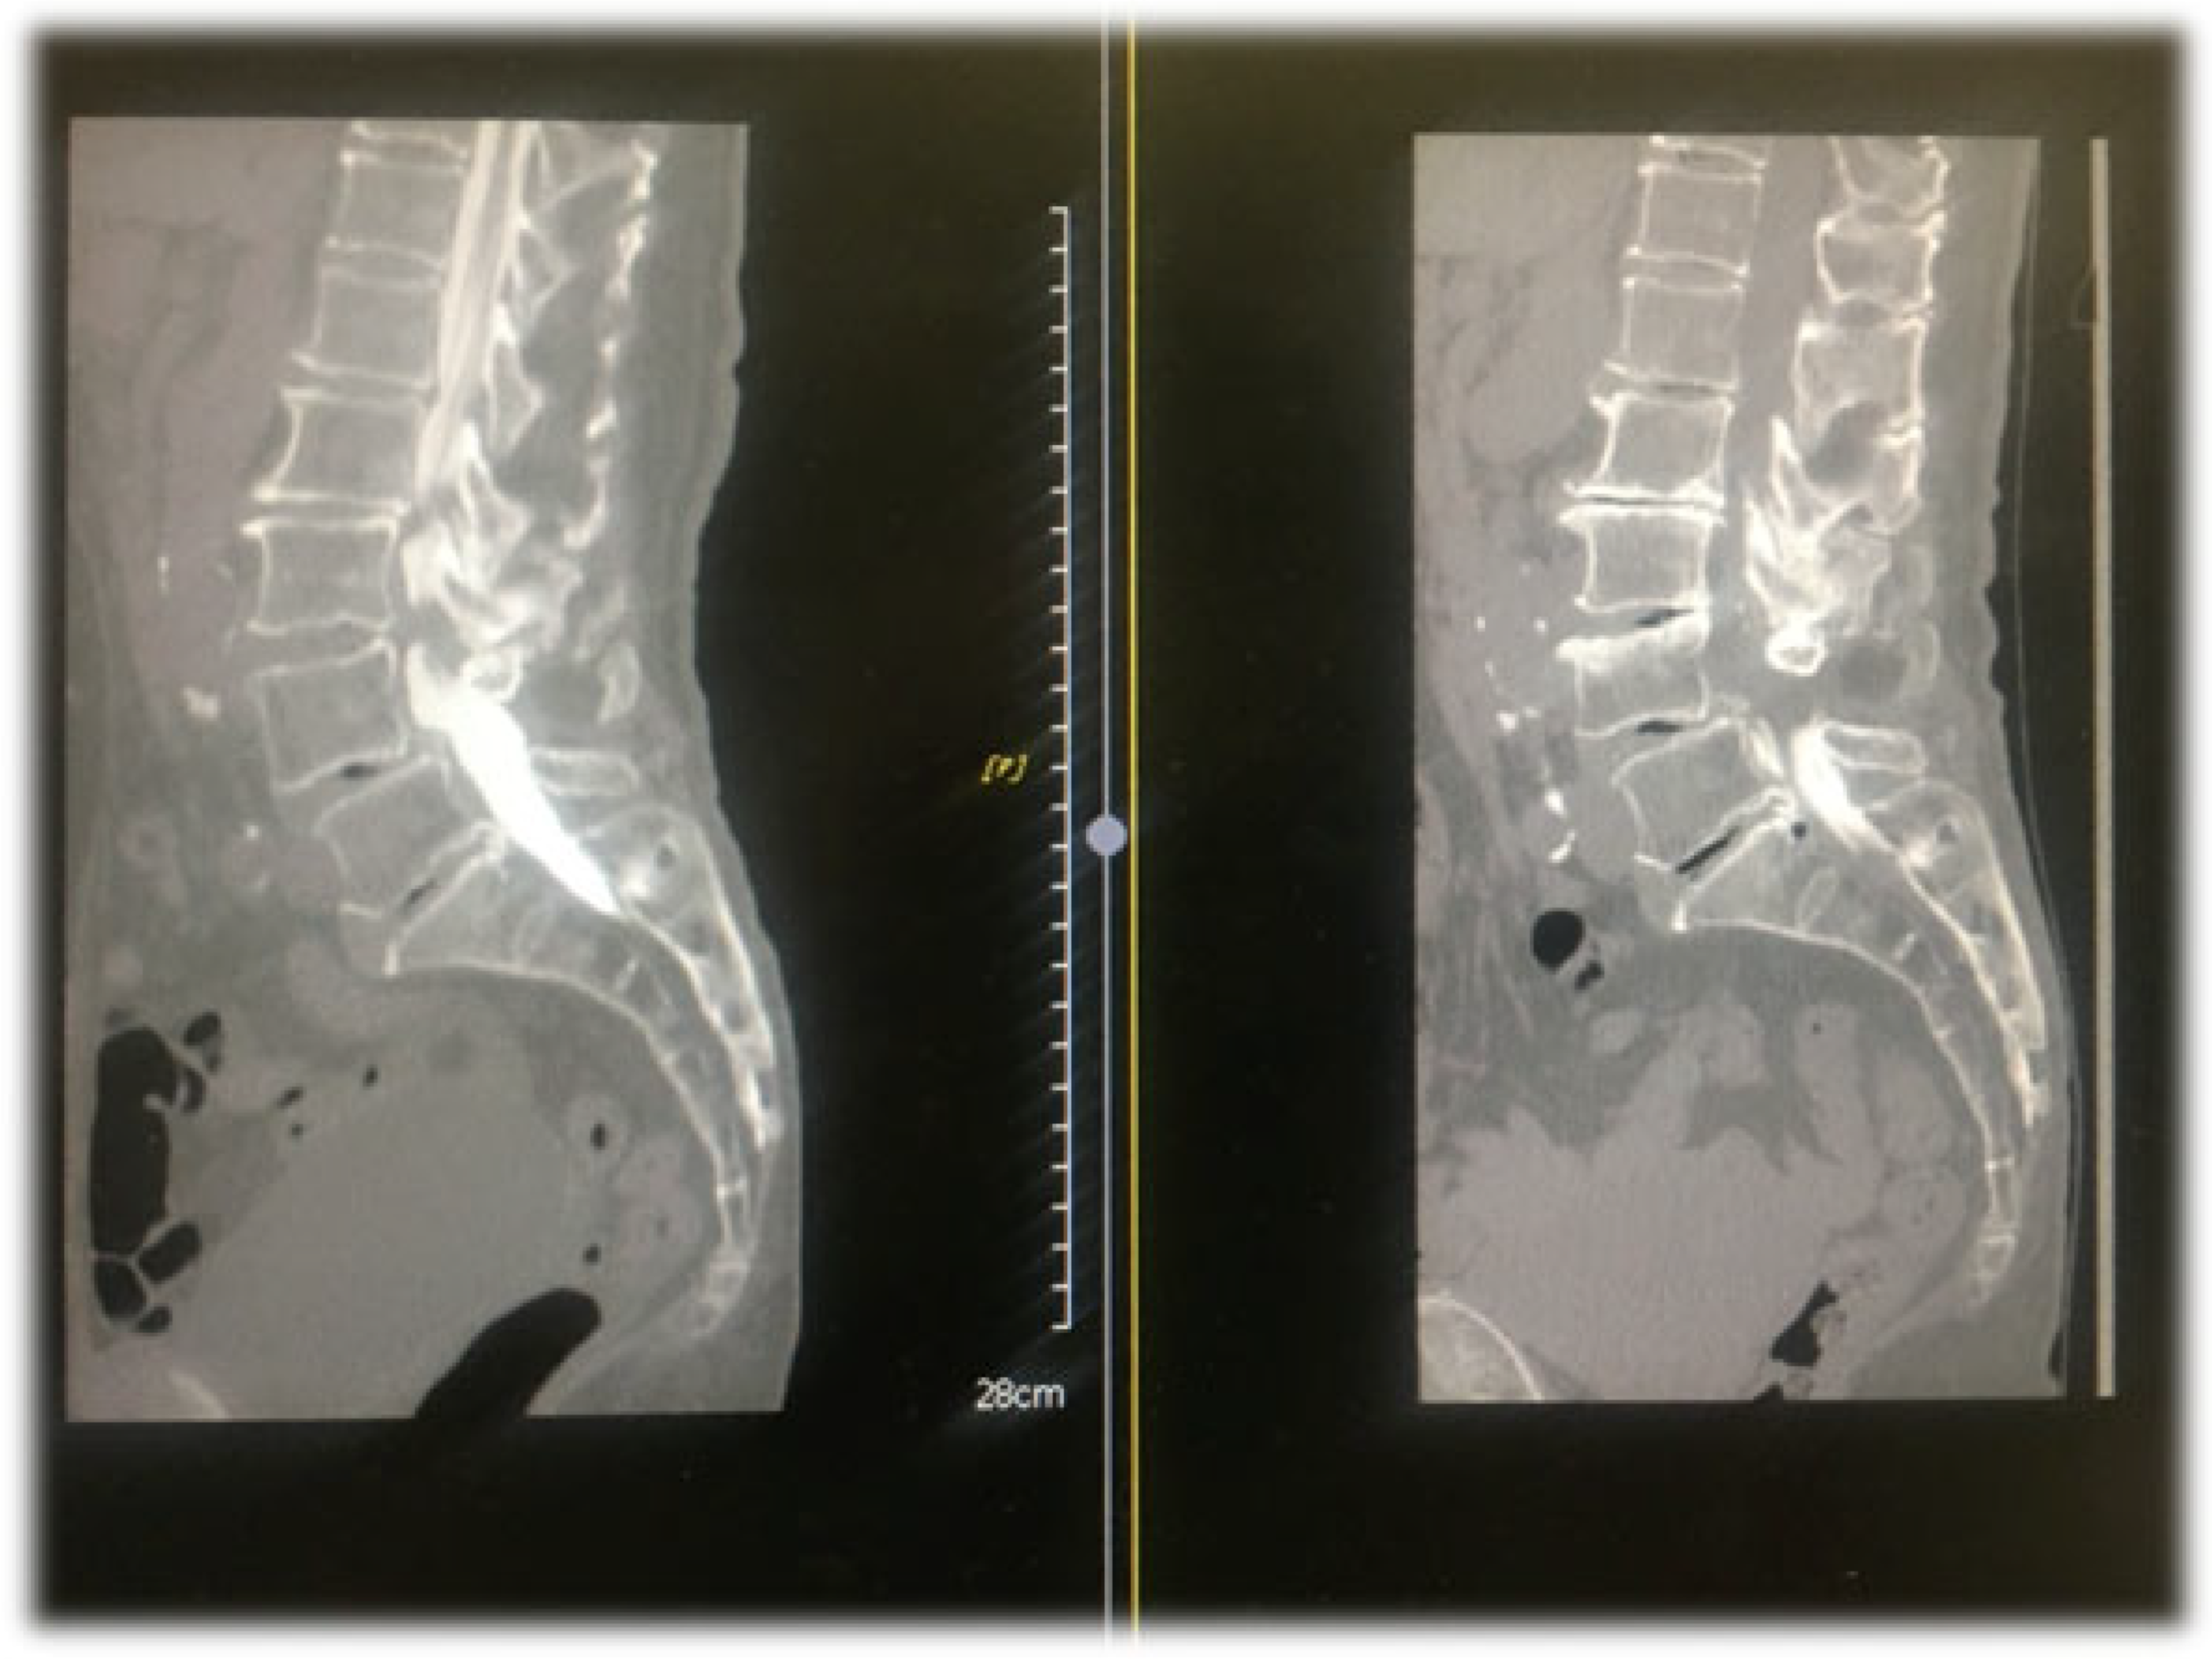

4.1. CT Epidurography